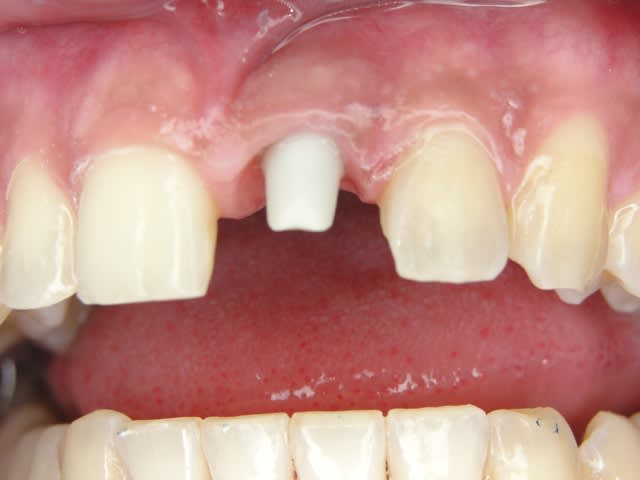

J'ai de tout en boutique..jeune homme 25 ans accident de piscine choc sur la bordure ( fêlure existante..fistule), extraction le jour même, temporisation 4 mois (avec un bout de trombone) Monobloc 16mm 60N, prep cap zircone droit 2/2 provisoire ion, temporisation 3 mois ceramo ceram..

J'ai de tout en boutique..jeune homme 25 ans accident de piscine choc sur la bordure ( fêlure existante..fistule), extraction le jour même, temporisation 4 mois (avec un bout de trombone) Monobloc 16mm 60N, prep cap zircone droit 2/2 provisoire ion, temporisation 3 mois ceramo ceram.. suite des photos :)

Au contraire..si tu regarde attentivement les radios tu veras qu'en quelques mois il y a une néoformation osseuse autour des micros spires. On voit un manque le jour de la pose et plus d'os avec la Procera. Volontairement j'ai pas plus enfoncé l'implant ..Si j'avais ouvert j'aurai bousillé tout le potentiel cicatriciel..Charon l'a démontré depuis longtemps en paro. Aux patient je leur explique que "Ouvrir c'est comme tondre le gazon avec un motoculteur" .

Donc il y maintien et renfort du parodonte.

Si à ça tu rajoutes "l'amitié" de la gencive avec le zircone il n'y a pas de raisons de perdre quoi que ce soit..